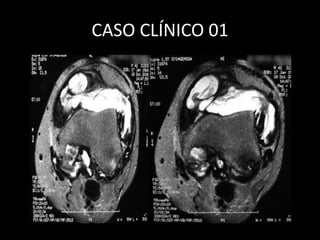

CASO CLÍNICO 01